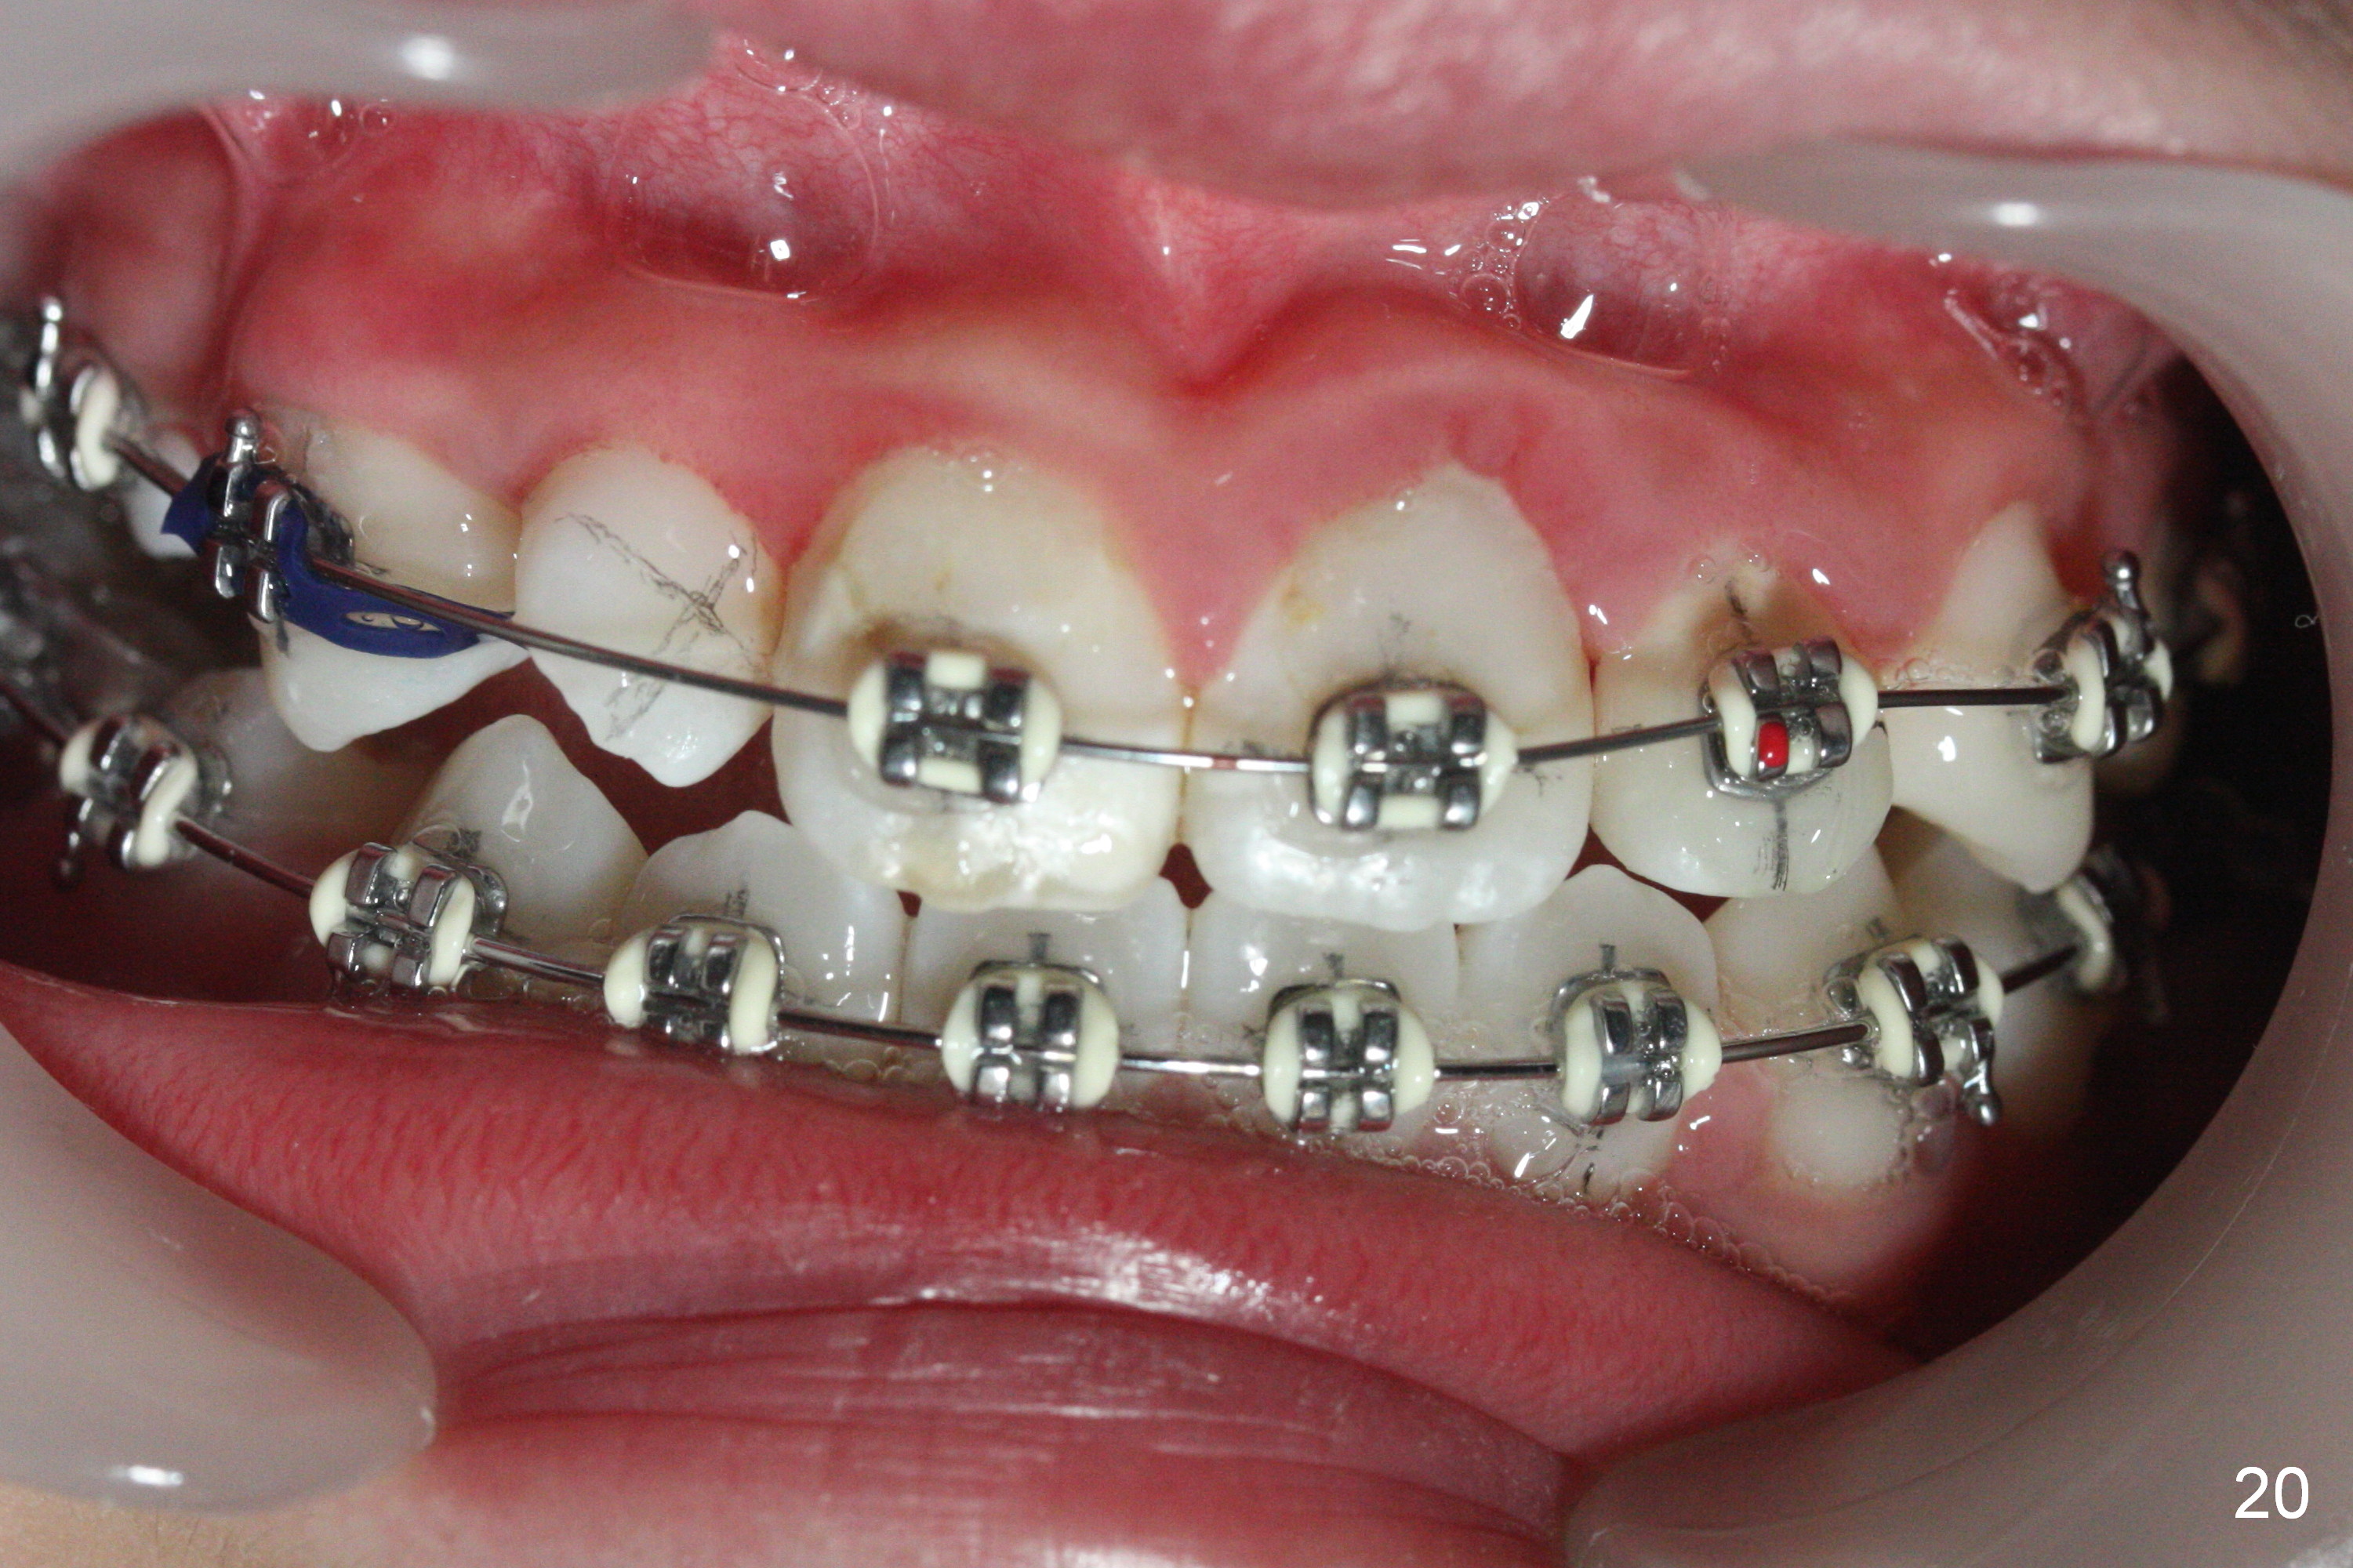

Three visits after open coil spring and 1 visit after sling shot, U2 cross bite is corrected (Fig.18,19). Due to UR2 rotation (Fig.19), bracket cannot be placed (Fig.20, 16 niti). Power chain x 3 is placed between UR2 and 3 to gain space for bracketing, which turns out not working. UL2 bracket is placed upside down for torque.